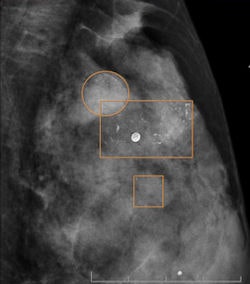

"On the other hand, that increase in detection was not directly attributable to CAD, because none of the readers recognized that CAD prompted a cancer not previously perceived by the radiologist," they wrote. "Thus, we recorded 25 type C recalls and none of them turned out to be cancer. Therefore, we think that the improvement in the performance of the program might be mainly related to the improvement in the readers."

Specialized breast radiologists performed better than general radiologists. Also, CAD did not detect any cancer not perceived previously by the radiologist, according to the authors.